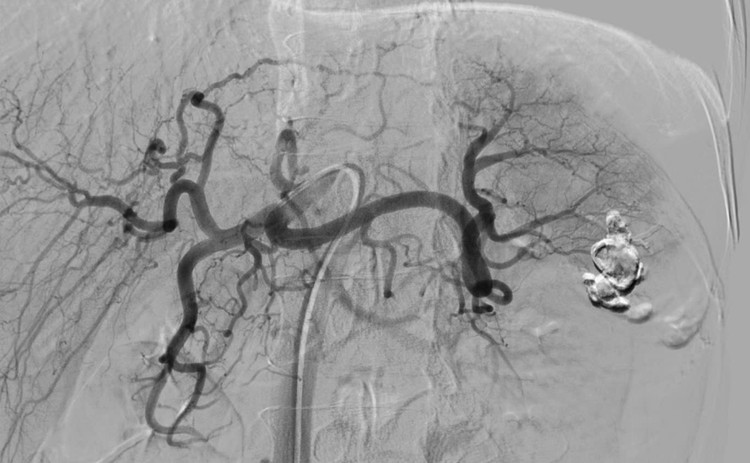

| Hình ảnh vỡ lách trên phim chụp - Ảnh BVCC |

Trước nguy cơ bệnh nhân có thể tử vong do shock mất máu, kíp trực cấp cứu tại phòng khám đã nhanh chóng hội chẩn toàn hệ thống, bệnh nhân được chuyển ngay về Bệnh viện Đa khoa Hùng Vương thực hiện can thiệp nút động mạch lách - Chụp và nút động mạch điều trị cầm máu các tạng số hóa xóa nền:

Nút tắc ổ chảy máu và cuống mạch mang, động mạch lách tổn thương bằng keo sinh học và Lipiodol/Vỡ lách độ IV có chảy máu hoạt động, tràn máu ổ bụng - đa chấn thương ngực bụng, gãy xương sườn trái.

Với hệ thống máy chụp mạch máu số hóa xóa nền (DSA), kíp can thiệp do Thạc sĩ, bác sĩ Trần Văn Kiên cùng ekip đã tiến hành can thiệp nút mạch cầm máu thành công cho bệnh nhân. Ca nút mạch diễn ra trong khoảng 15 phút, sau can thiệp bệnh nhân ổn định, không cần truyền máu.